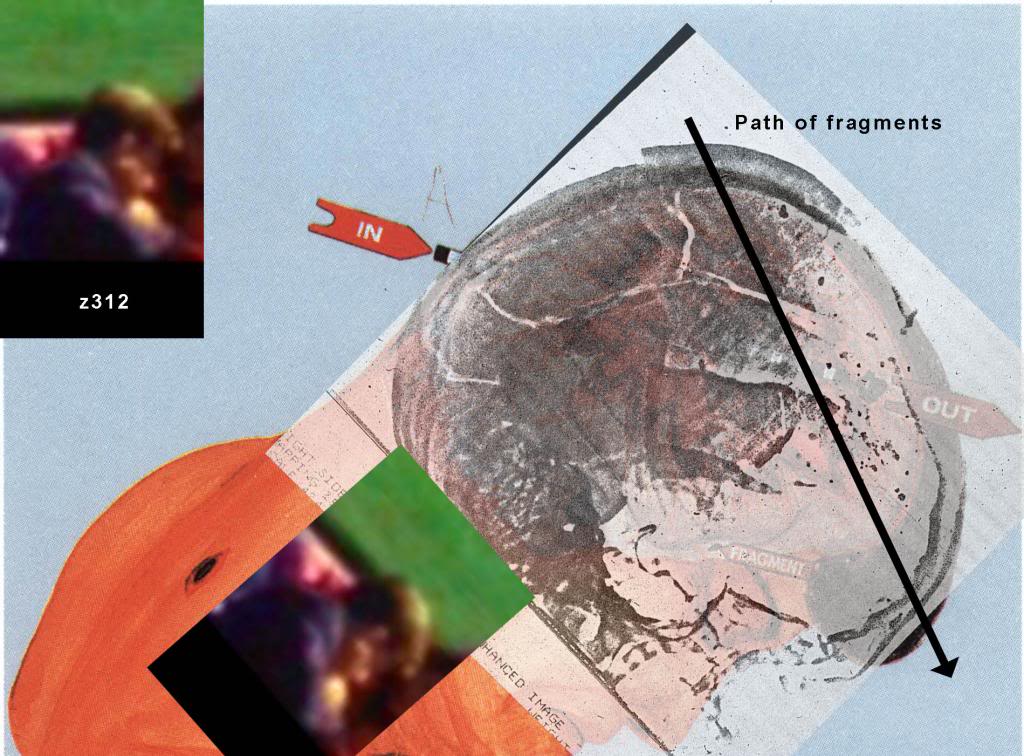

Commander HUMES - The X-rays made of the wound in the head of the late President showed fragmentations of the missile. Some fragments we recovered and turned over, as has been previously noted. Also we have X-rays of the fragment of skull which was in the region of our opinion exit wound showing metallic fragments.

http://mcadams.posc.mu.edu/russ/testimony/humes.htm (Archiv-Version vom 11.03.2016)Man erkennt sogar Fracture lines, die vom "occiput" ausgehen. Und da dieselben Pathologen auch den autopsiebericht geschrieben haben, in dem die "fractures" erwähnt werden, haben sie sich die Röntgenaufnahmen unter diesem Aspekt auch angeschaut

The third obvious wound at the time of the examination was a

huge defect over the right side of the skull.

This defect involved BOTH the scalp and the underlying SKULL, and from the brain substance was protruding.

This wound measured approximately

13 centimeters in greatest diameter.

http://www.history-matters.com/archive/jfk/arrb/master_med_set/pdf/md1.pdfHow did a 17-cm skull defect on the night of the autopsy shrink in the autopsy report? Boswell told the HSCA, [360] the ARRB, and one of the authors (Aguilar, in a recorded call)[361] that it all had to do with the aforementioned beveled bone fragment. The skull defect started out at 17-cm., but after the fragment was replaced into the backside of JFK’s skull, the remaining gap then measured “only” 13-cm., the dimension cited in the autopsy report.